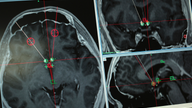

Chinese researchers try brain implants to treat addiction

The sound of doctors boring through his skull to feed electrodes deep into his brain made Yan tremble.